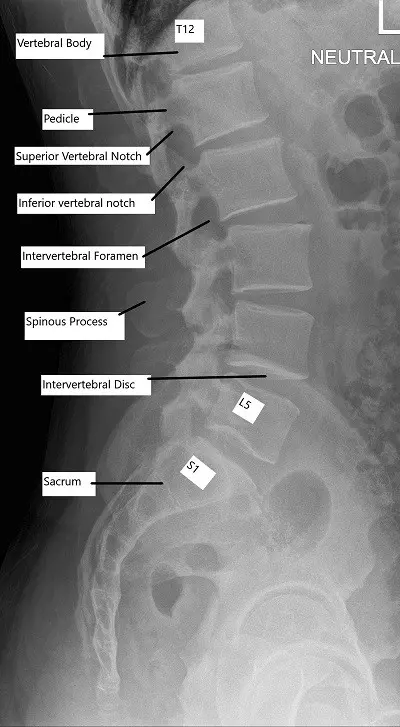

Visión general de la imagen

Las radiografías proporcionan una visualización básica de la alineación de la columna vertebral y la integridad ósea. Los TAC ofrecen imágenes detalladas de las estructuras óseas y son útiles en traumatismos o afecciones degenerativas. La RM es la mejor herramienta de diagnóstico por imagen para evaluar los tejidos blandos, incluidos los discos intervertebrales, los ligamentos, las raíces nerviosas y la médula espinal.